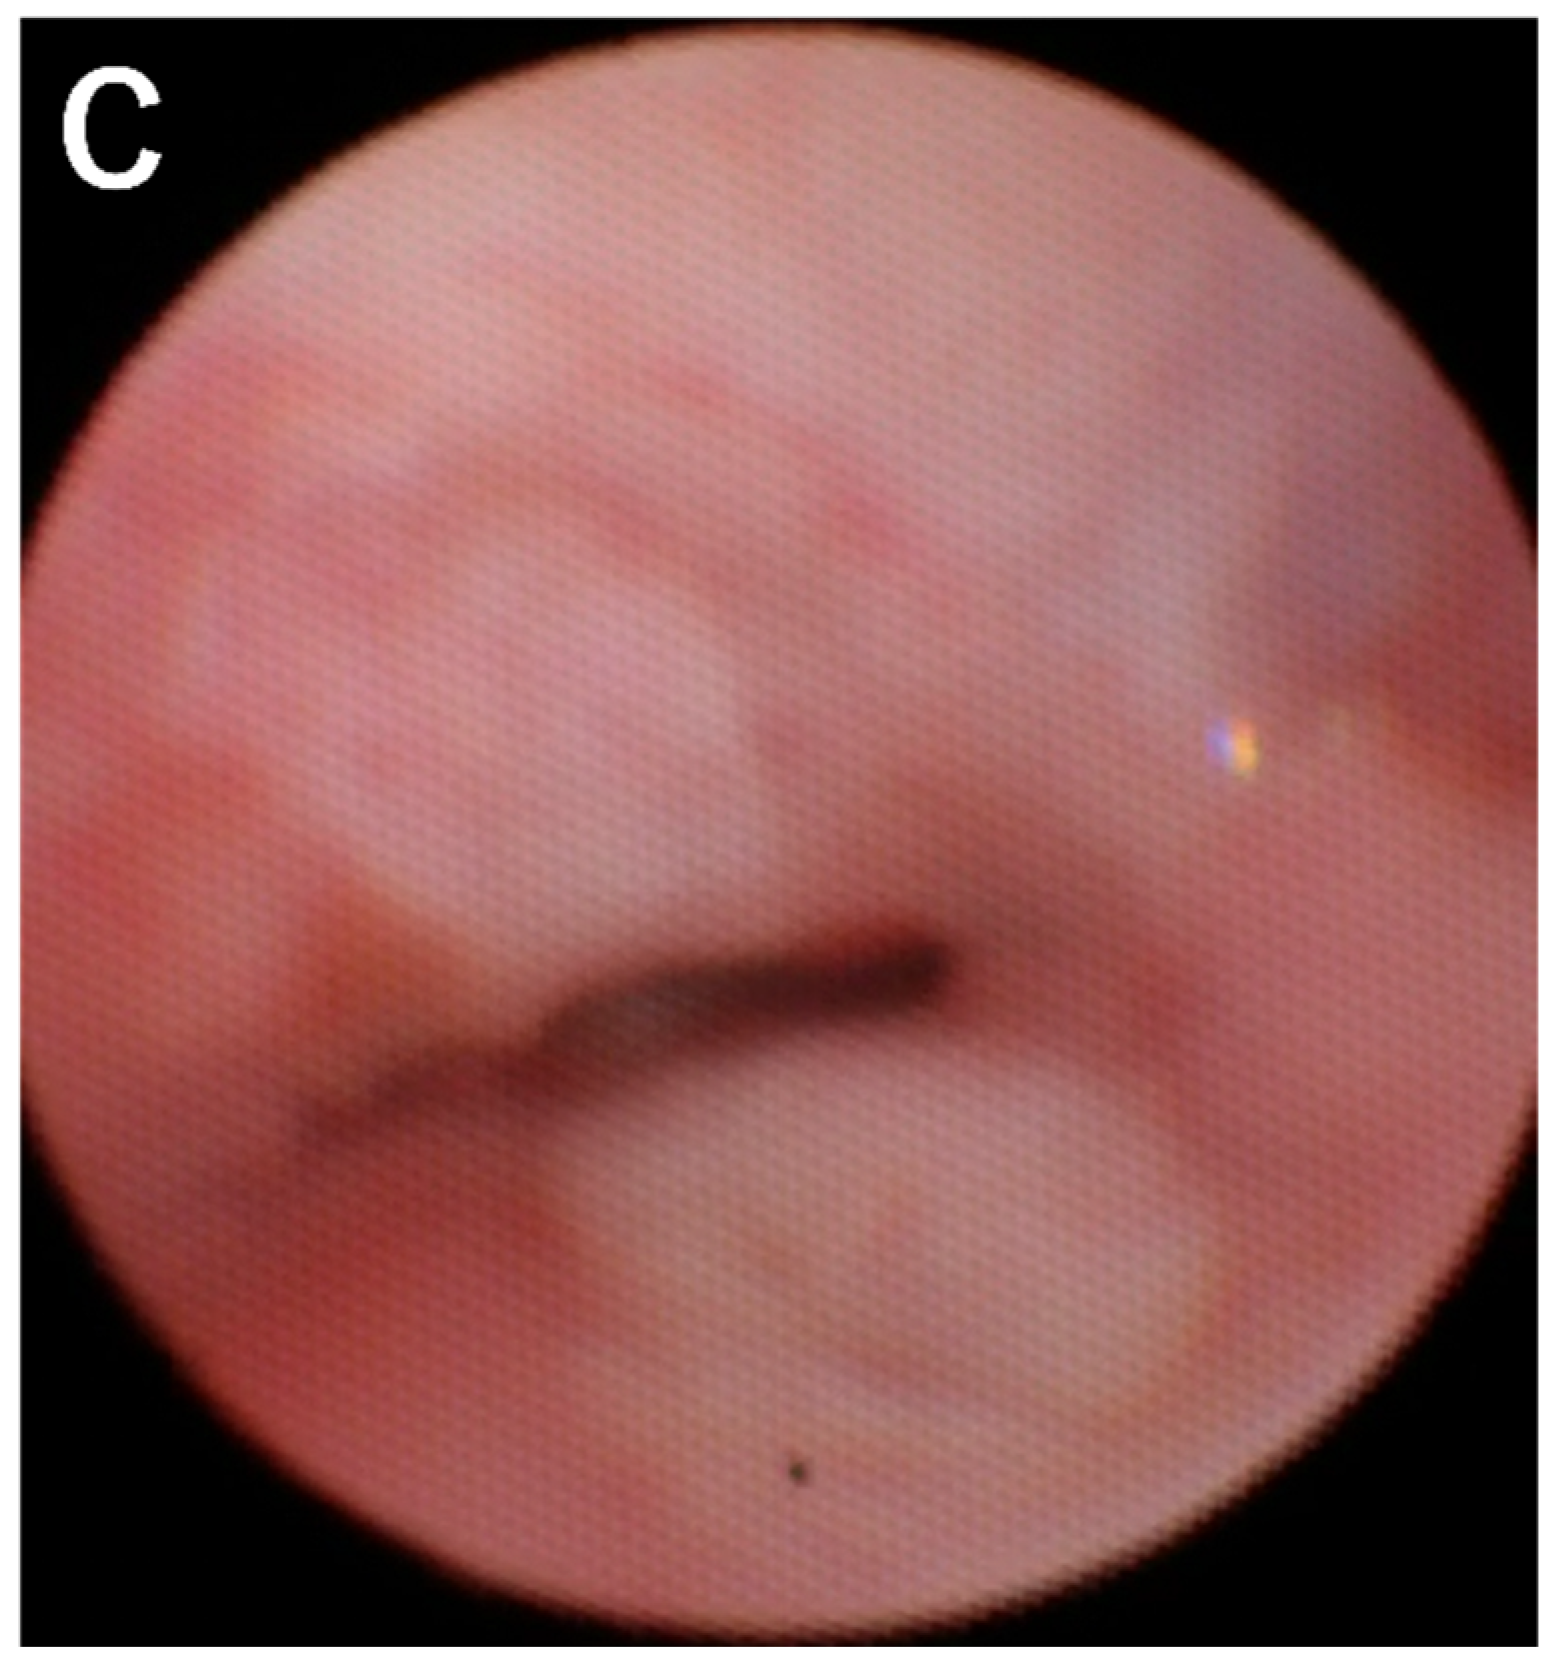

2. Case Description